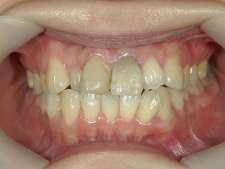

矯正歯科 治療後矯正歯科 プチワイヤー矯正 治療後矯正歯科(プチワイヤー矯正)治療後

矯正歯科 治療後  スペース確保の為、 2番抜歯

no.37_7548_治療後_右.JPGno.37_7548_治療後_正面.JPGno.37_7548_治療後_左.JPG